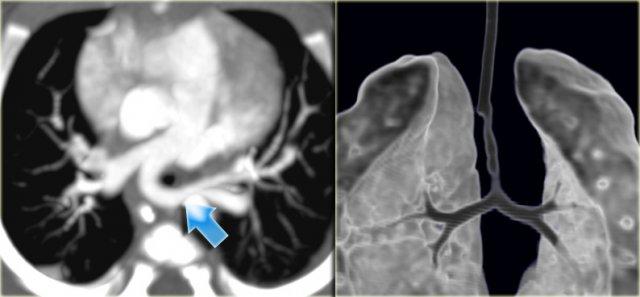

On the left an adolescent with a murmur.

On axial image and reconstruction the patent ductus arteriosus is seen.

The ductus arteriosus is the communication between the pulmonary artery and the proximal descending aorta.

It shunts blood in utero from the right ventricle to the aorta to bypass the non-functioning lungs.

On the first day of life there is a functional closure and an anatomic closure with fibrosis in the first two weeks.

If it does not close these patients come to attention either with a murmur or later with pulmonary hypertension.

On the left a young adult with a murmur.

The cardiologists are not interested in the flow direction, but just want to confirm the diagnosis.

Notice the connection between the pulmonary artery and the descending aorta.

When the duct closes it may also calcify.

This a normal variant.